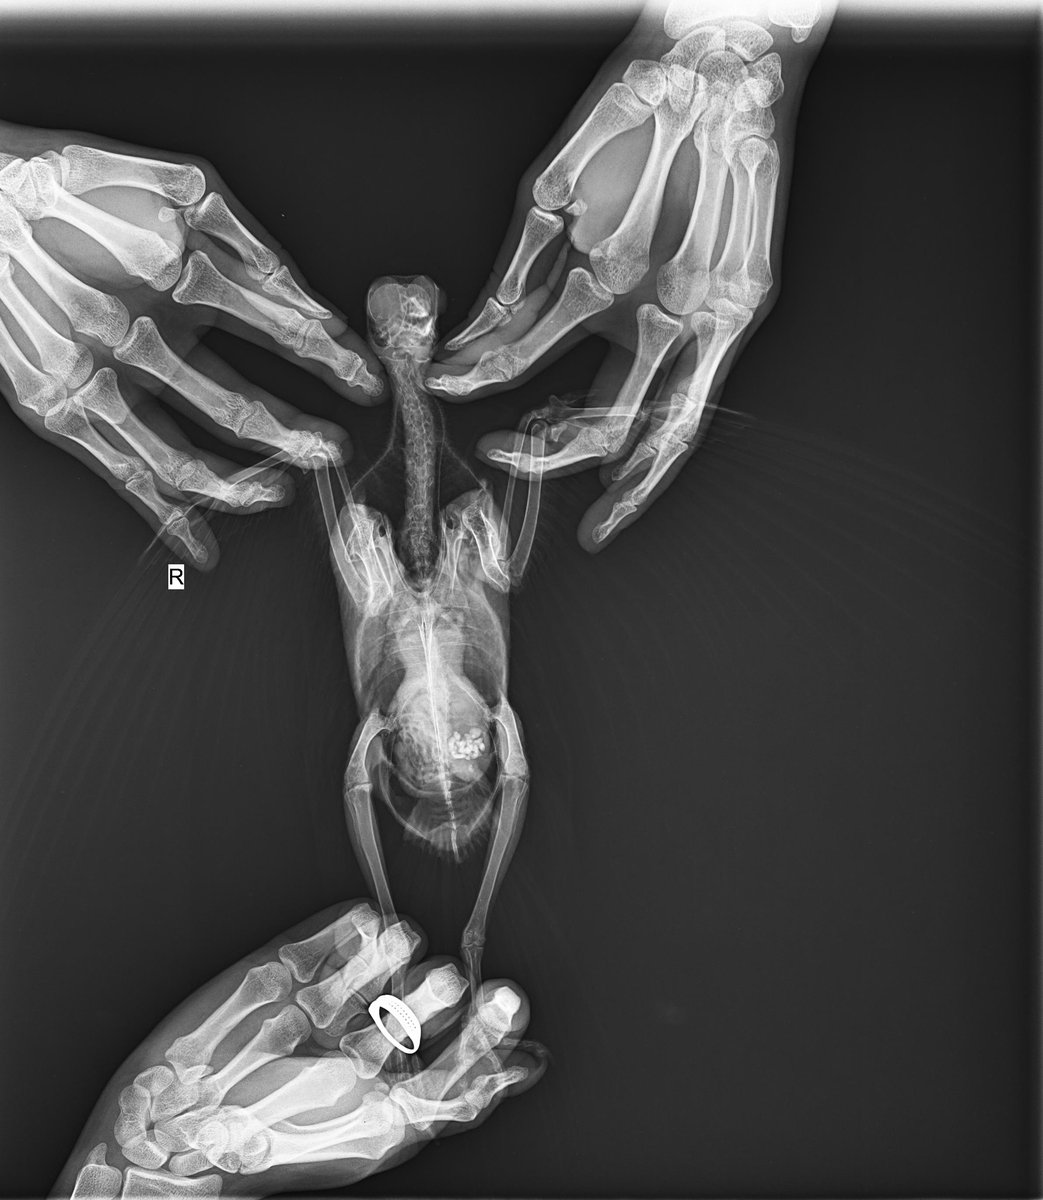

Appleness Опубликовано 28 января, 2022 Автор #46 Опубликовано 28 января, 2022 (изменено) @маленький принц сегодня в 13:30 идем ко врачу, он поставит диагноз и назначит лечение. 8:00 покормила кашей из шприца, перья немного почистила, помет все тот-же ярко-темно-зеленый, без крови рассмотрела сегодня горло, там совсем маленькая дырочка для глотания, ему тяжело глотать большие объемы @маленький принц я понимаю, что вы хотите помочь, но тут несколько врачей, все пишут разное, я не понимаю кого мне слушать. На приеме спрошу сегодня про орнидазол и метрогил. @OFA @Zosia можете рентген посмотреть, я так и не поняла, можно по нему как-то диагноз ставить или хотя бы что-то исключить? У меня получилось рассмотреть рот У него есть язык, но он скрыт под чем-то непонятным. Это или опухоль, или киста, или что-то еще. у этого чего-то есть темное пятно, но в целом оно светлое, размеров с шарик около 5мм. Именно это образование мешает глотать, и не дает проникнуть в горло ватной палочкой. Во рту слизи нет. попробую его покормить инсулиновым шприцом, справа(со стороны голубя ) рта есть доступ к горлу, слева этот шарик Изменено 28 января, 2022 пользователем Appleness

маленький принц Опубликовано 28 января, 2022 #48 Опубликовано 28 января, 2022 1 час назад, Appleness сказал: У него есть язык, но он скрыт под чем-то непонятным. Это или опухоль, или киста, или что-то еще. у этого чего-то есть темное пятно, но в целом оно светлое, размеров с шарик около 5мм. Именно это образование мешает глотать, и не дает проникнуть в горло ватной палочкой. это и есть нарост можете сделать фото и СРОЧНО начать лечение читайте про трихоминоз https://www.mybirds.ru/forums/topic/65174-trihomonoz/ 1 час назад, Appleness сказал: @Zosia можете рентген посмотреть, я так и не поняла, можно по нему как-то диагноз ставить или хотя бы что-то исключить? рентген у Вас получился просто идеальный если Зося на нём что-то заметила бы она бы написала 41 минуту назад, Appleness сказал: 8:45 получилось! инсулиновый шприц вставила в горло (в голубе был только кончик шприца, толстая часть снаружи). раньше я просто наливала в рот жидкую кашу, много разбрызгивалось. сейчас получается всю кашу ввести в голубя. и поэтому кашу я сделала уже более густую. через три часа после кормёжки нужно фото помёта кончик шприца перед кормлением смазать снаружи Метрогил-дента